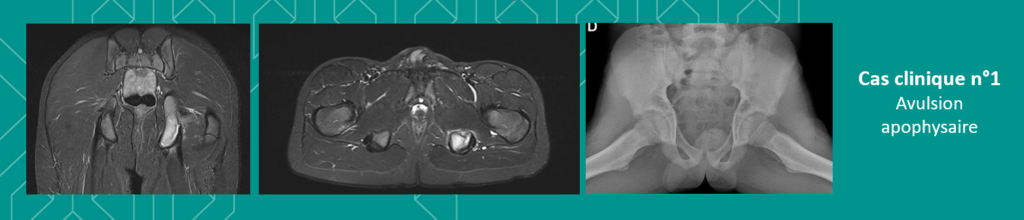

🔹N°1 – Jeune garçon âgé de 12 ans : à la suite d’un traumatisme au football et un mouvement en hyperextension de la cuisse, accompagné d’une douleur d’horaire mécanique au niveau de la fesse gauche, la radiographie révèle une petite irrégularité de la tubérosité ischiatique gauche avec un aspect un peu flou qui pourrait être inquiétante en absence d’éléments cliniques. L’IRM confirme le diagnostic d’avulsion apophysaire, une lésion assez classique chez l’enfant sportif.